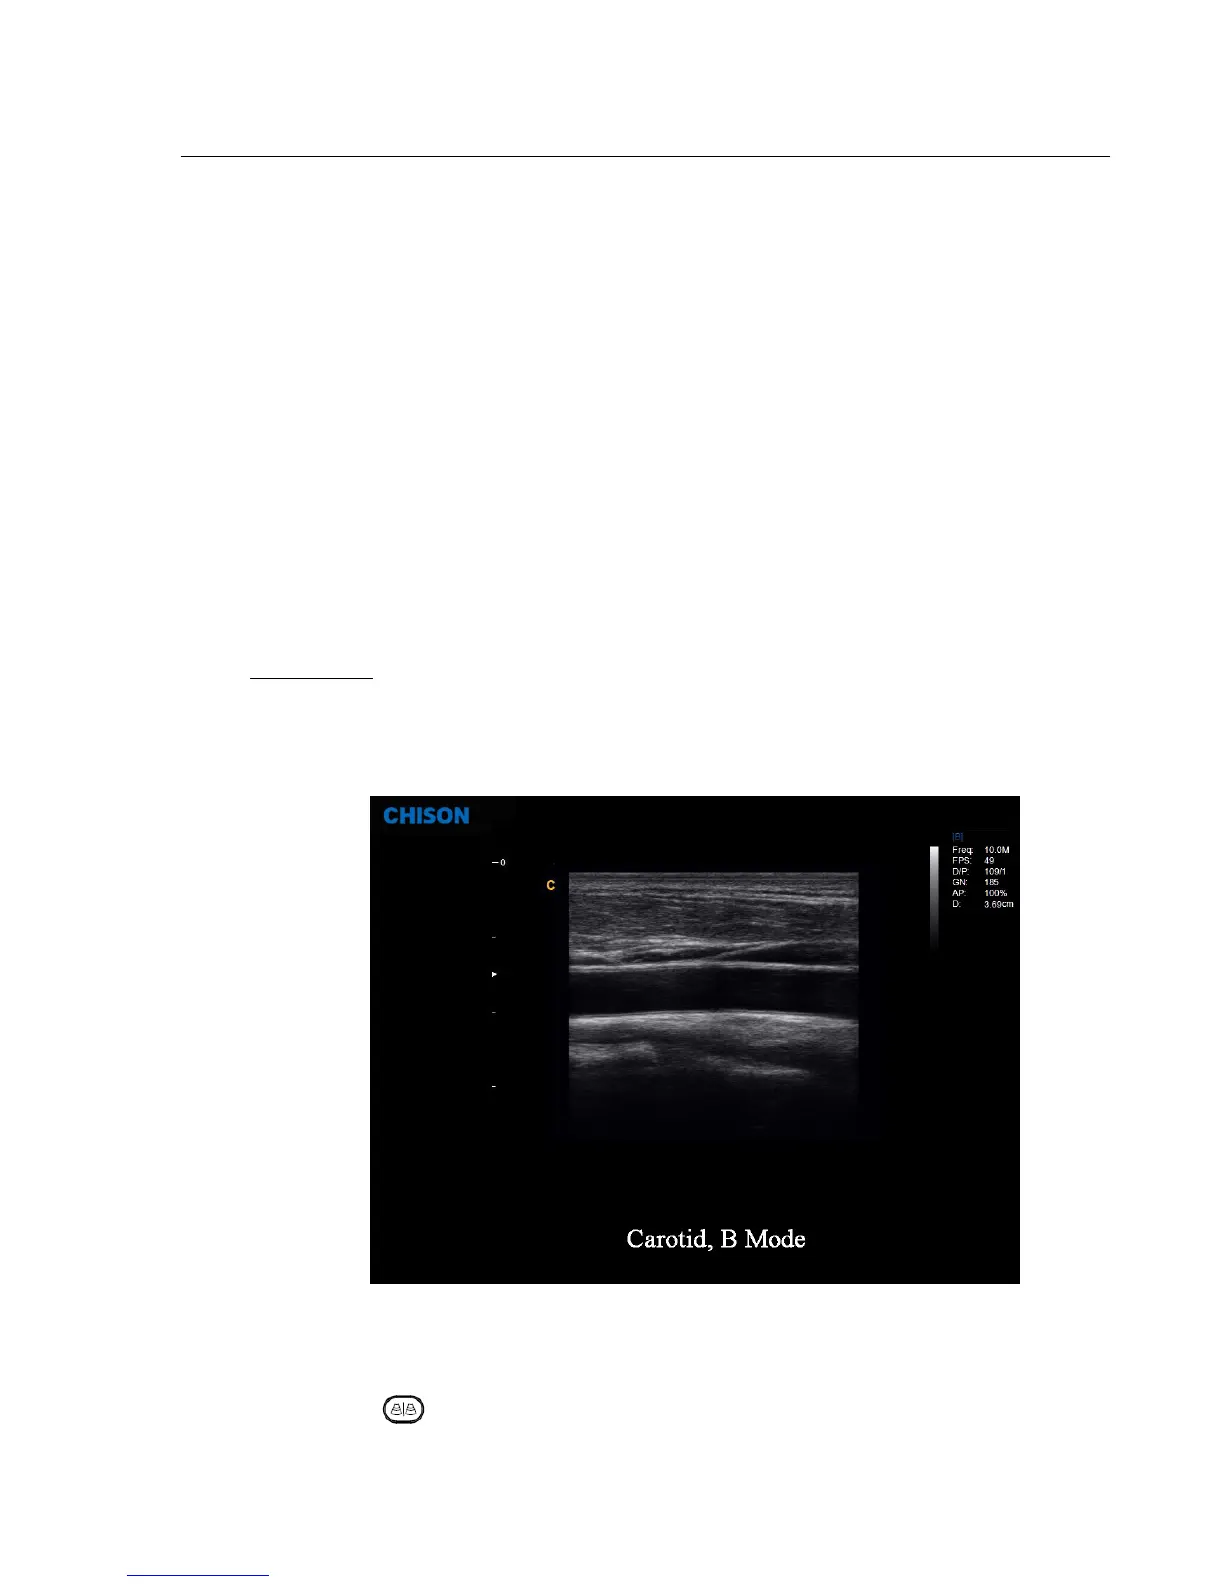

4.3.3. B Mode

B-mode is intended to provide two-dimensional images and measurement capabilities concerning the

anatomical structure of soft tissue. Press B -knob to enter into B mode. Rotate B-knob to adjust B gain.

Fig. 4-6 B Mode